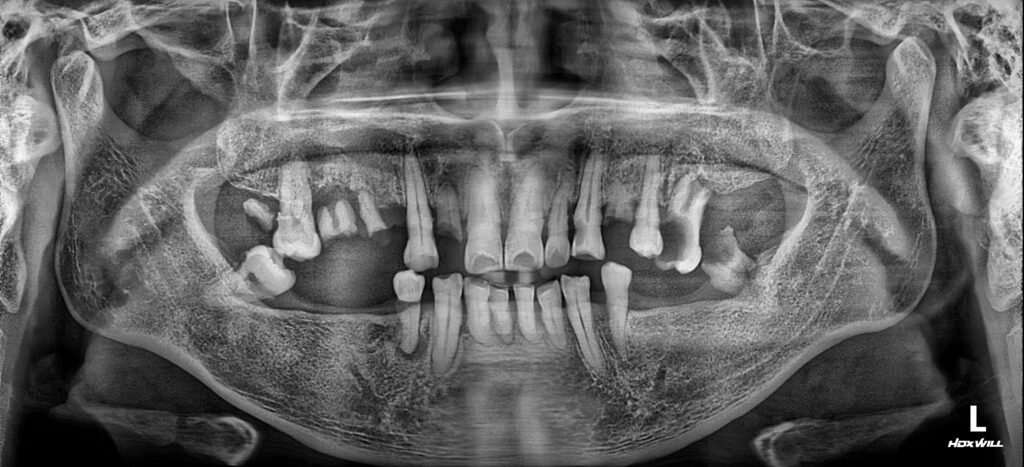

처음 내원하셨을 때 촬영한 파노라마 사진입니다.

대다수의 치아가 치주질환과 치아우식이 발생한 상태였는데요. 거의 빠질듯한 치아가 매우 많으셨습니다.

영도치과 서울화이트S치과는 최대한 살릴 수 있는 치아는 보존적 치료를 통해 살리고, 저작기능을 주로하는 어금니 부위는 단단하고 안정적인 임플란트 식립을 하는 것으로 치료계획을 세워드렸습니다.